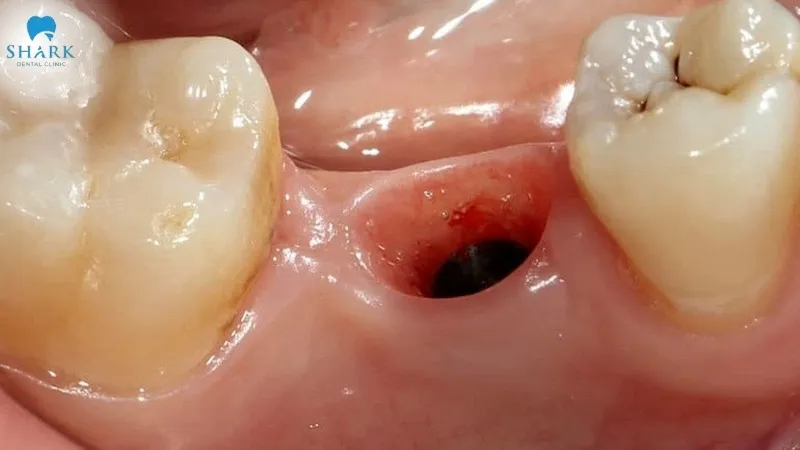

Visual characteristics of a healthy blood clot after tooth extraction

Recognizing the signs of a healthy blood clot is essential for monitoring your healing progress and preventing potential complications.

The blood clot does not remain unchanged; it undergoes gradual color changes throughout the healing process, which are as follows:

- First 24 hours: The blood clot appears dark red as it fills the extraction socket to stop the bleeding.

- 24–48 hours: The clot turns dark brown or black as its surface begins to dry and contract.

- 3–7 days: A whitish or pale yellow layer develops, which is granulation tissue that supports healing and is not pus.

- 7–14 days: The extraction site becomes light pink, resembling normal gum tissue, indicating that healing is largely progressing well.